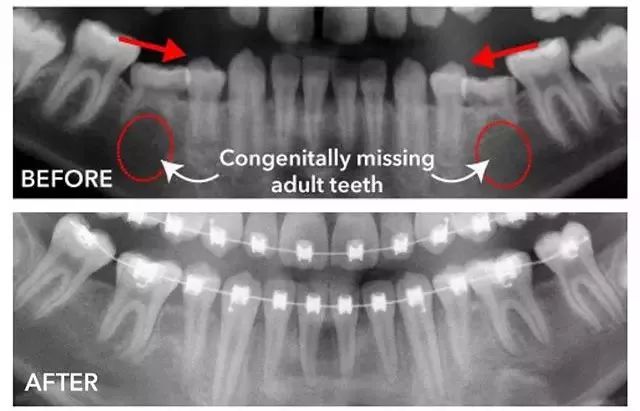

- 可能存在恒牙的先天缺失。

- 这种情况需要到医院借助X线片来判断,如果确定先天缺失,正畸医生会根据周围牙齿的排列情况选择合适时机、恰当方法进行治疗。